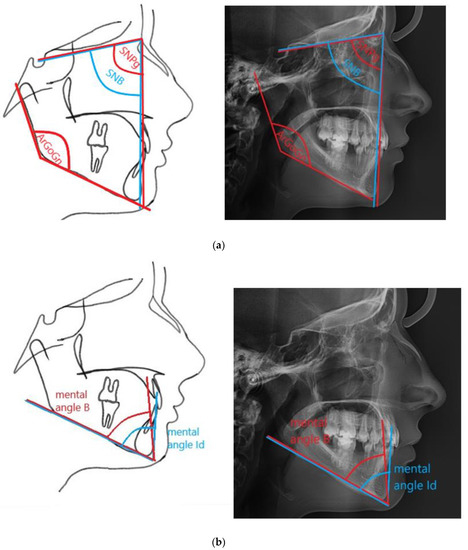

| ArGoGn | The mandibular angle, the angle betweenArGo andGoGn lines |

| Mental angle B | The angle between the ML mandibular plane and PgB line, determining the anteroposterior position of the B point, relative to the Pg point (the authors’ measurement) |

| Mental angle Id | The angle between the ML mandibular plane and the PgId line, determining the anteroposterior position of the Id point, relative to the Pg point |

| SNB | The angle determined by the SN and NB lines that determines the anteroposterior position of the mandible |

| SNPg | The angle determined by the SN and NPg lines that determines the anteroposterior position of the chin |